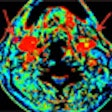

Perfusion CT handily distinguishes malignant neck nodes